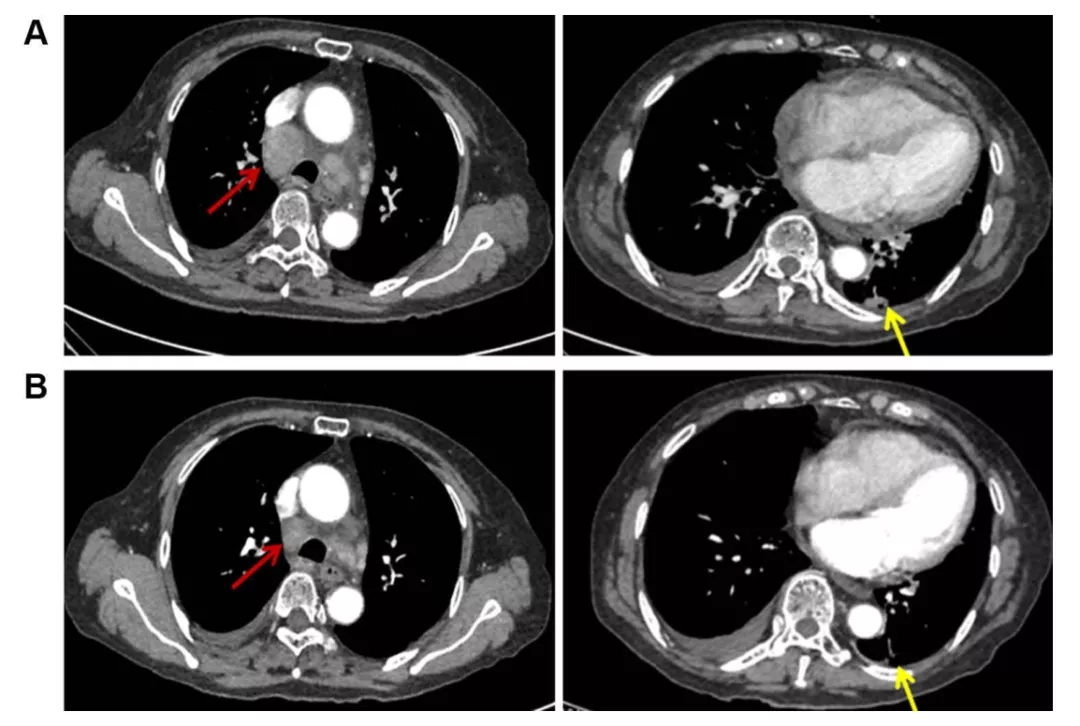

与上述多靶点抗血管生成药物相似,安洛替尼也主要通过抑制VEGFR1-3和成纤维细胞生长因子受体(FGFR)1-4。本文中三个临床案例均具有TP53突变,接受安罗替尼治疗后效果均为PR。基于这些以上数据,TP53突变患者可能是安罗替尼获益人群。当然更需要一个更大的临床前瞻性的随机对照试验来确认!小火苗,大希望!期待这一发现成为我们打开TP53突变肿瘤治疗的契机!